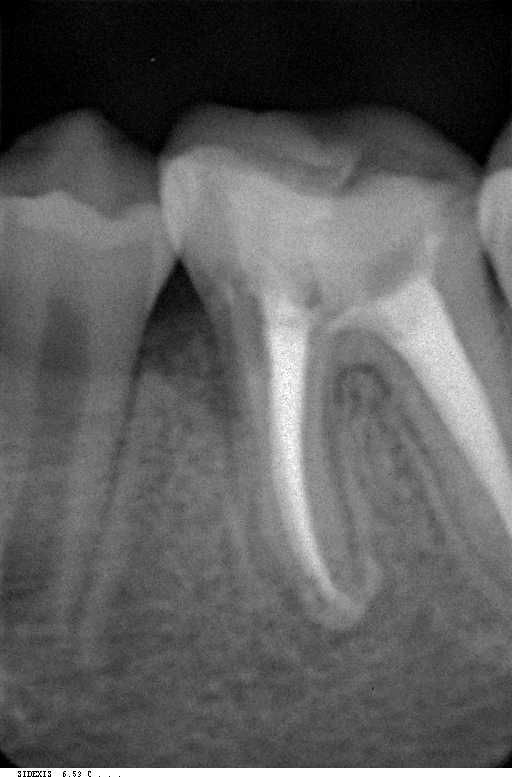

*Далее идет обтурация корневого канала, который предназначен для "уплотнения" против будущего вторжения бактерий, которые могут повторно заразить зуб и, следовательно, ставят под угрозу лечение корневого канала.

До лечения Во время лечения Спустя 6 мес

Для проверки правильности процедур берется одна или несколько “контрольных” рентгенограмм. Несмотря на то, что многие считают Эндодонтическое лечение завершенным после обтурации корневого канала, есть по крайней мере два одинаково важных шага для здоровья и долголетия зуба.